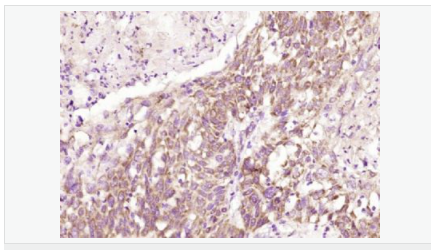

| 产品应用 | WB=1:500-2000 ELISA=1:5000-10000 IHC-P=1:100-500 IHC-F=1:100-500 ICC=1:100-500 IF=1:100-500 (石蜡切片需做抗原修复) not yet tested in other applications. optimal dilutions/concentrations should be determined by the end user. |

| 产品介绍 | This gene encodes a type I transmembrane protein and is a tumor-specific endothelial marker that has been implicated in colorectal cancer. The encoded protein has been shown to also be a docking protein or receptor for Bacillus anthracis toxin, the causative agent of the disease, anthrax. The binding of the protective antigen (PA) component, of the tripartite anthrax toxin, to this receptor protein mediates delivery of toxin components to the cytosol of cells. Once inside the cell, the other two components of anthrax toxin, edema factor (EF) and lethal factor (LF) disrupt normal cellular processes. Three alternatively spliced variants that encode different protein isoforms have been described. [provided by RefSeq, Oct 2008] Function: Plays a role in cell attachment and migration. Interacts with extracellular matrix proteins and with the actin cytoskeleton. Mediates adhesion of cells to type 1 collagen and gelatin, reorganization of the actin cytoskeleton and promotes cell spreading. Plays a role in the angiogenic response of cultured umbilical vein endothelial cells. Subunit: Interacts with gelatin and type 1 collagen. Interacts with the actin cytoskeleton. Binds to the protective antigen (PA) of Bacillus anthracis. Binding does not occur in the presence of calcium. Subcellular Location: Cell membrane; Single-pass type I membrane protein. Cell projection, lamellipodium membrane; Single-pass type I membrane protein. Cell projection, filopodium membrane; Single-pass type I membrane protein. Note=At the membrane of lamellipodia and at the tip of actin-enriched filopodia. Colocalizes with actin at the base of lamellipodia. Tissue Specificity: Detected in umbilical vein endothelial cells (at protein level). Highly expressed in tumor endothelial cells. DISEASE: Defects in ANTXR1 are associated with susceptibility to hemangioma capillary infantile (HCI) [MIM:602089]. HCI are benign, highly proliferative lesions involving aberrant localized growth of capillary endothelium. They are the most common tumor of infancy, occurring in up to 10% of all births. Hemangiomas tend to appear shortly after birth and show rapid neonatal growth for up to 12 months characterized by endothelial hypercellularity and increased numbers of mast cells. This phase is followed by slow involution at a rate of about 10% per year and replacement by fibrofatty stroma Similarity: Belongs to the ATR family. Contains 1 VWFA domain. SWISS: Q9H6X2 Gene ID: 84168 Database links: Entrez Gene: 84168 Human Entrez Gene: 69538 Mouse Omim: 606410 Human SwissProt: Q9H6X2 Human SwissProt: Q9CZ52 Mouse Unigene: 165859 Human Unigene: 232525 Mouse Unigene: 41192 Rat Important Note: This product as supplied is intended for research use only, not for use in human, therapeutic or diagnostic applications. |